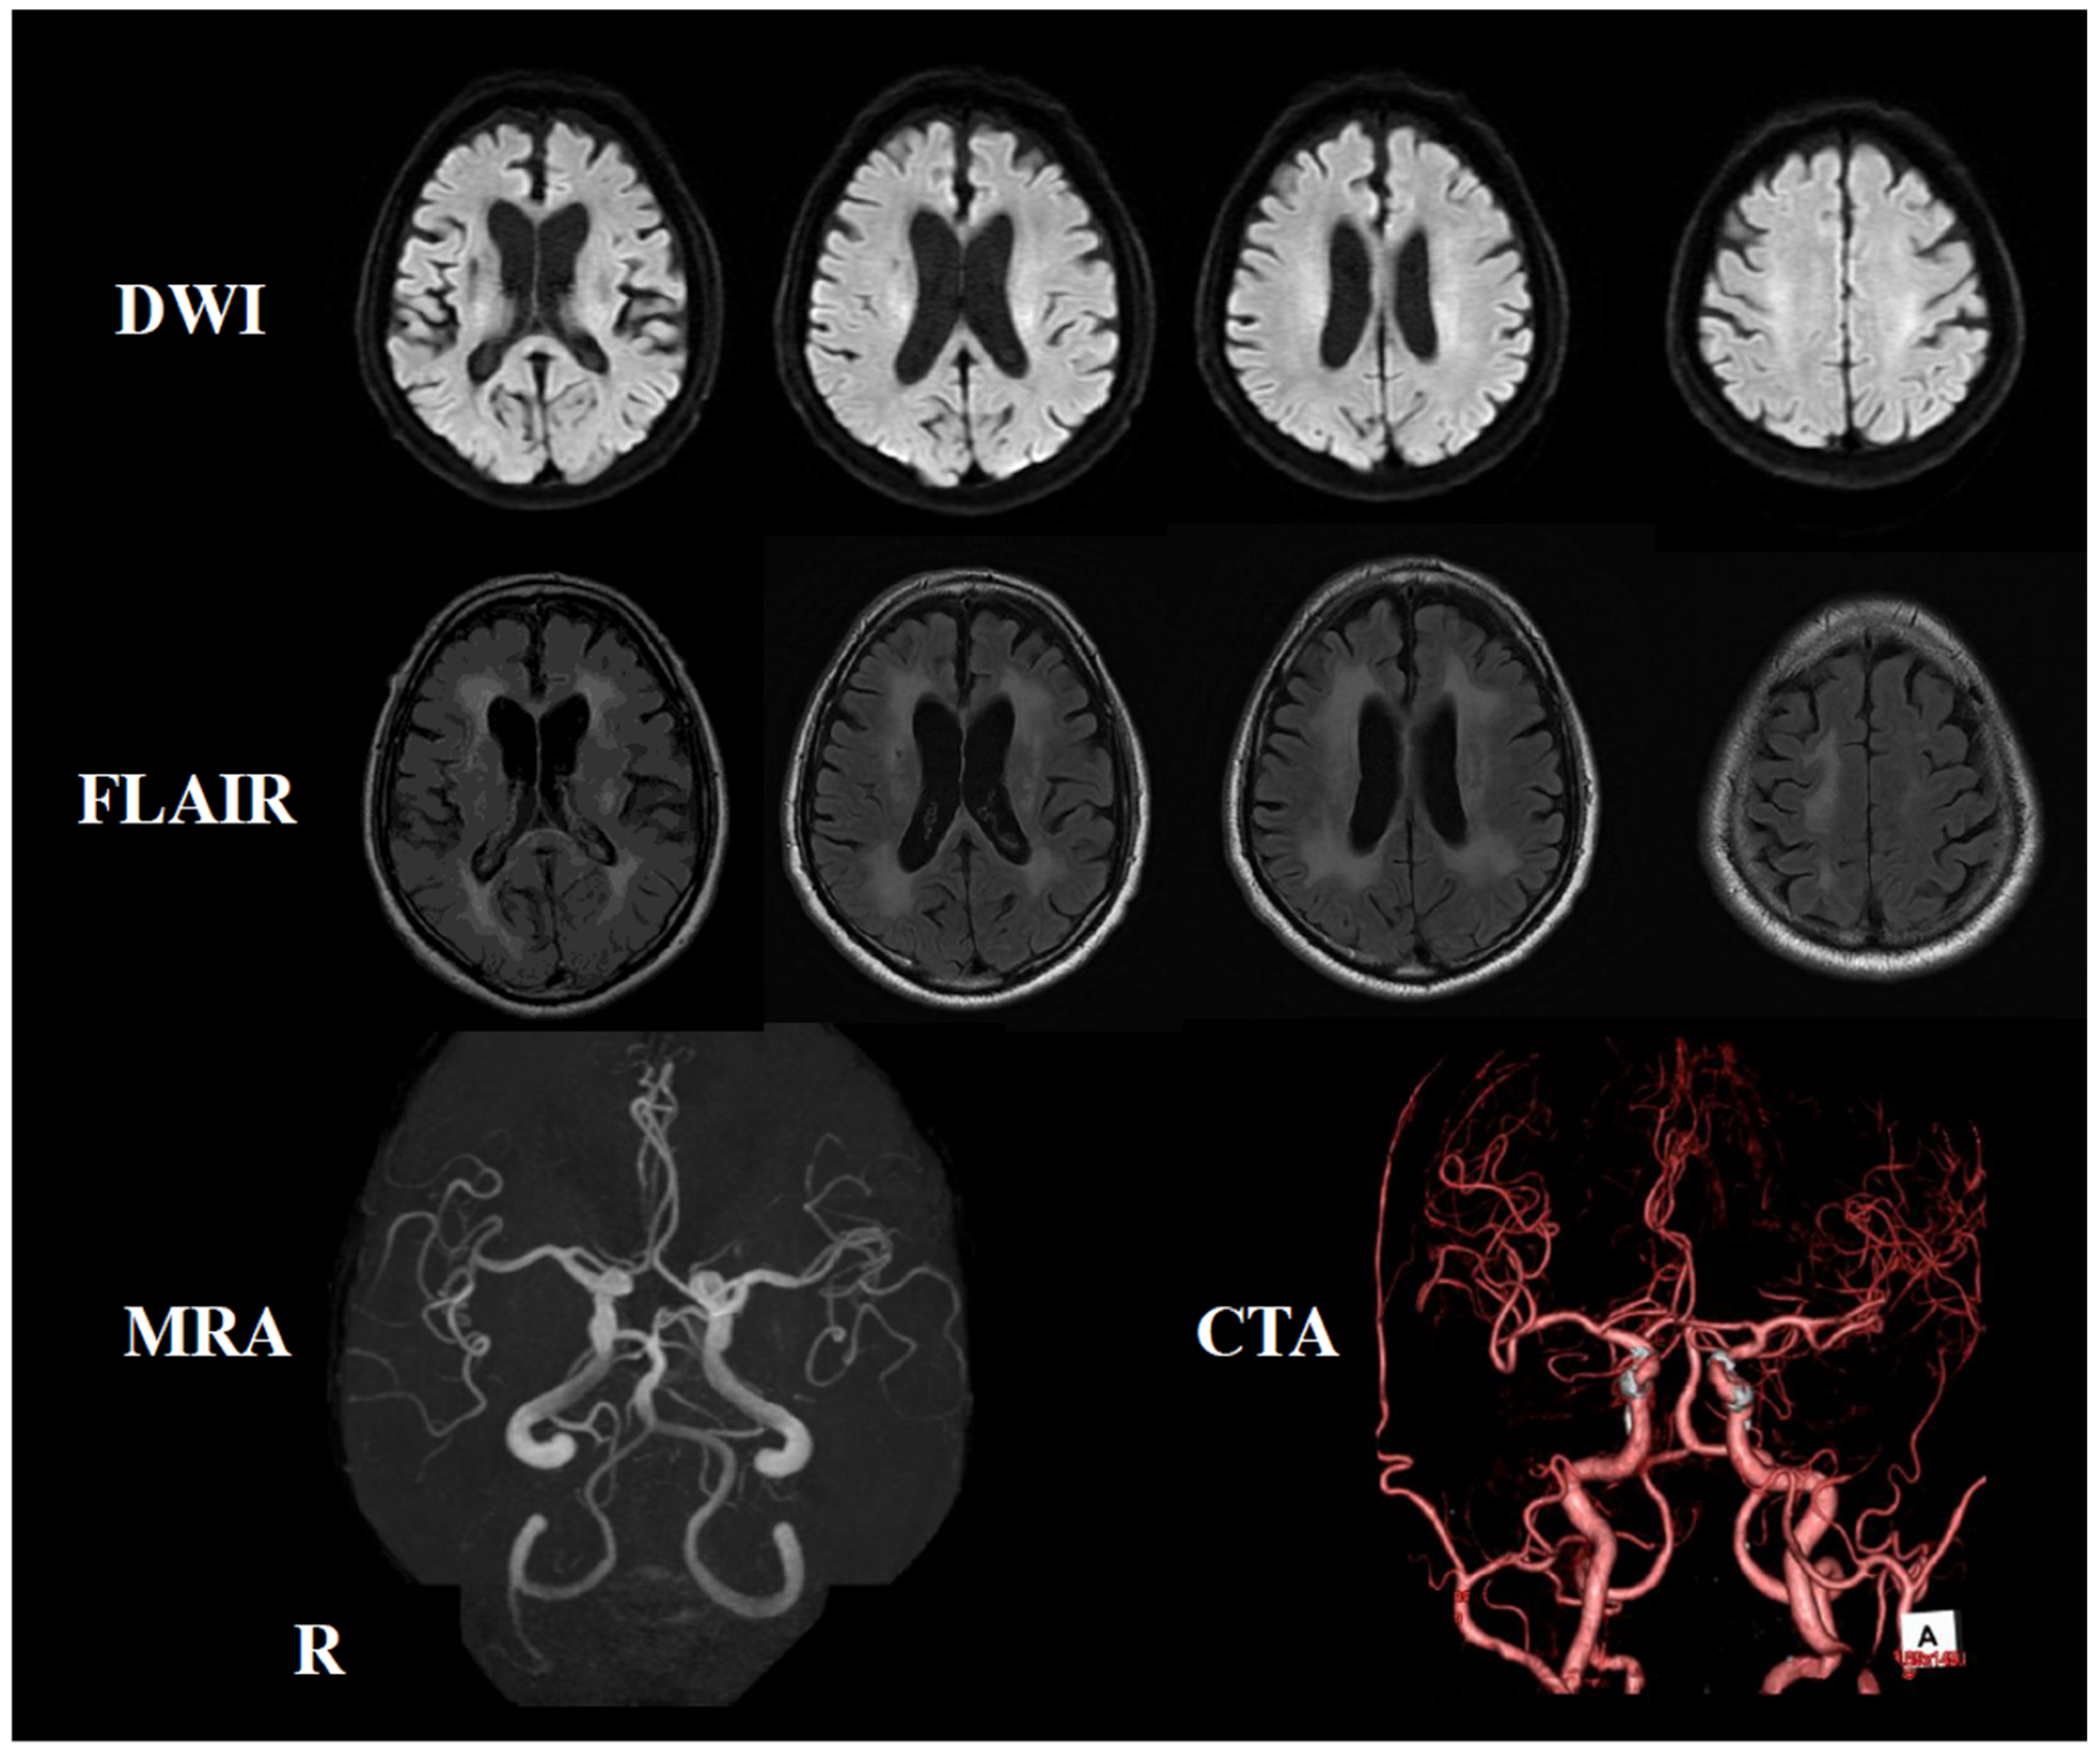

2. Case Presentation